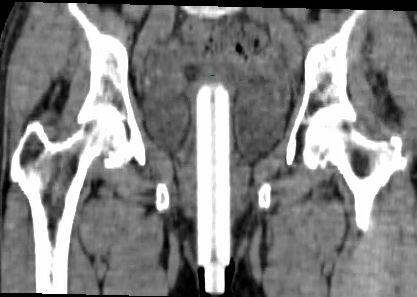

Hysterectomy- 1st step in endometrial cancer

• 5 types: based on extent of surgery

• Type I: removes uterus/cervix only (most common for uterine cancer)

• Type V: removes uterus, cervix, vagina, bladder, rectum

Anatomy After Hysterectomy